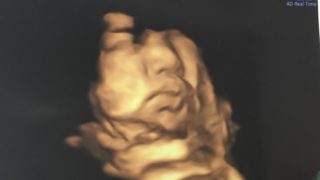

第10回 妊婦検診 4d カンジダ再発 臨月の体の変化 Ramの妊娠記録 体外から授かりました からの育児記録